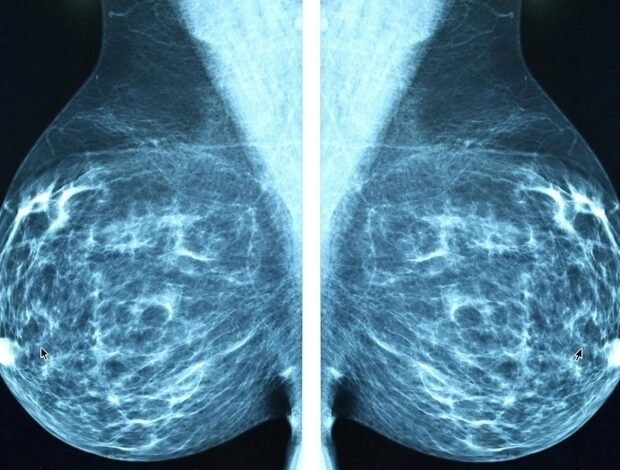

A estratégia de leitura híbrida para a triagem de mamografia reduz o ônus do trabalho do radiologista

Uma estratégia para a leitura híbrida para examinar a imagem de mamíferos, que os pesquisadores holandeses foram recuperados retrospectivamente por mais de 40.000 testes, reduziu o trabalho do trabalho no radiologista em 38 % sem alterar as taxas de detecção de câncer. O estudo, que enfatiza a confiança da inteligência artificial, foi publicado hoje em RaioJornal da Associação de Radiação da América do Norte (RSNA).

Sarah d. Ferbum, candidato a doutorado no Departamento de Fotografia Médica do Centro Médico da Universidade Radbod, na Holanda: “Embora o desempenho geral de modelos de inteligência artificial no mais recente estilo muito alto, a inteligência artificial às vezes cometa erros”. “Determinando os exames que a interpretação da inteligência artificial não é confiável. É muito importante permitir e melhorar o uso de modelos de inteligência artificial Exame de câncer de mama Programas. “

Para desenvolver e avaliar uma estratégia de leitura mista, os pesquisadores usaram um conjunto de dados de 41.469 dados de exames de mama de 1522 mulheres (idade média de 59 anos) com 332 cânceres descobertos na tela e 34 cânceres de separação. Os exames foram realizados entre 2003 e 2018 em Utrecht, na Holanda, como parte do Programa Nacional de Exame de Câncer de Mama Holandês.

Entre as escalas de incerteza que foram avaliadas pelos pesquisadores, a entrada média do POM no grau na área mais suspeita da taxa de detecção de câncer de 6,6 por 1000 casos e uma taxa de chamada de 23,7 por 1000 casos, como taxas de leitura dupla padrão por radiologistas.

A estratégia final de leitura híbrida da Anistia Internacional incluiu a avaliação de todas as imagens de mama X -Ray para produzir dois diretores: POM e incerteza dessa previsão. Quando a inteligência artificial determinou que o POM era menor que o esqueleto em vigor, a questão era considerada normal. Quando descobri a inteligência do POM acima do limite especificado, as mulheres foram chamadas para mais testes, mas somente quando essa previsão estava confiante. Caso contrário, o exame foi de leitura dupla por radiologistas.

Embora a maioria das decisões de inteligência artificial não tenha sido confirmada e adiada para o leitor humano, 38 % foram classificados como certos e podem ser lidos apenas por inteligência artificial. Usando a estratégia dos pesquisadores, reduza a carga de ler um radiologista para 61,9 % sem alterar a convocação (23,6 ‰ em comparação com 23,9 ‰) ou taxas de detecção de câncer (6,6 ‰ em comparação com 6,7 ‰), ambas semelhantes às da leitura dupla padrão.

Quando o modelo de inteligência artificial foi confirmado, a área abaixo da curva (AUC) era superior (0,96 versus 0,87). Sua sensibilidade era quase idêntica à leitura de radiologista dupla (85,4 % em comparação com 88,9 %). Mulheres mais jovens com seios grossos eram mais propensos a serem incertos.